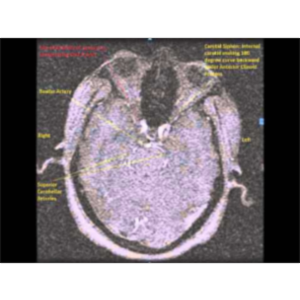

This is an MR angiography sequence of a 46-year old male patient who was being investigated for TIA. The image sequence shows 2-D Time of Flight (TOF) Spoiled Gradient Recall (SPGR) Echo Acquisition images. It shows the Vertebrobasilar and Carotid systems of Cerebral circulation. An incidental finding was abnormal Right Vertebral artery - Narrow, Double, One branch communication with Right Internal Carotid....

Educational value: Not seen in a regular textbook - A description from a patient's file, with permission - Rare findings